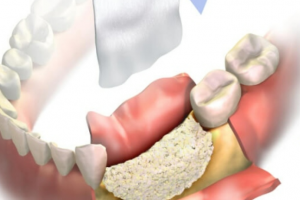

Tiêu Xương Hàm: Liệu Có Thể Niềng Răng Không?

Tiêu xương hàm là một tình trạng bệnh lý ảnh hưởng đến xương hàm và sức khỏe răng miệng. Điều này có thể gây ra nhiều vấn đề như mất răng, lệch cắn hoặc mất thẩm mỹ. Vậy người bị tiêu xương hàm có thể niềng răng không? Cùng SHINING SMILE tìm hiểu nhé.